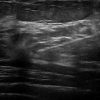

Ung thư vú - Ảnh 4

Ung thư vú

» Thông tin: Nữ giới – 62 tuổi.

» Lâm sàng: Kiểm tra sức khỏe.